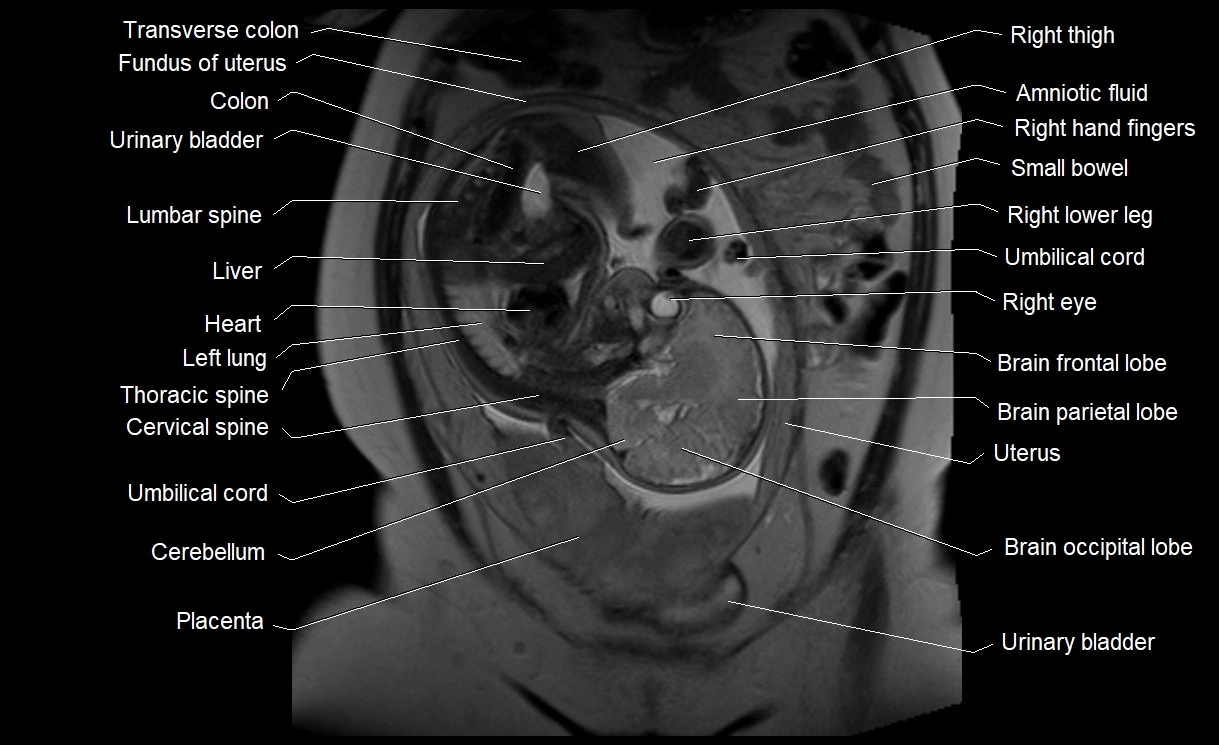

MRI Appearance

T2 HASTE (T2 GRE):

• Amniotic fluid shows very bright hyperintense signal

• Provides natural contrast against fetus and placenta

• Small particles (vernix) may appear as scattered hypointense foci within bright fluid

MRI image

image